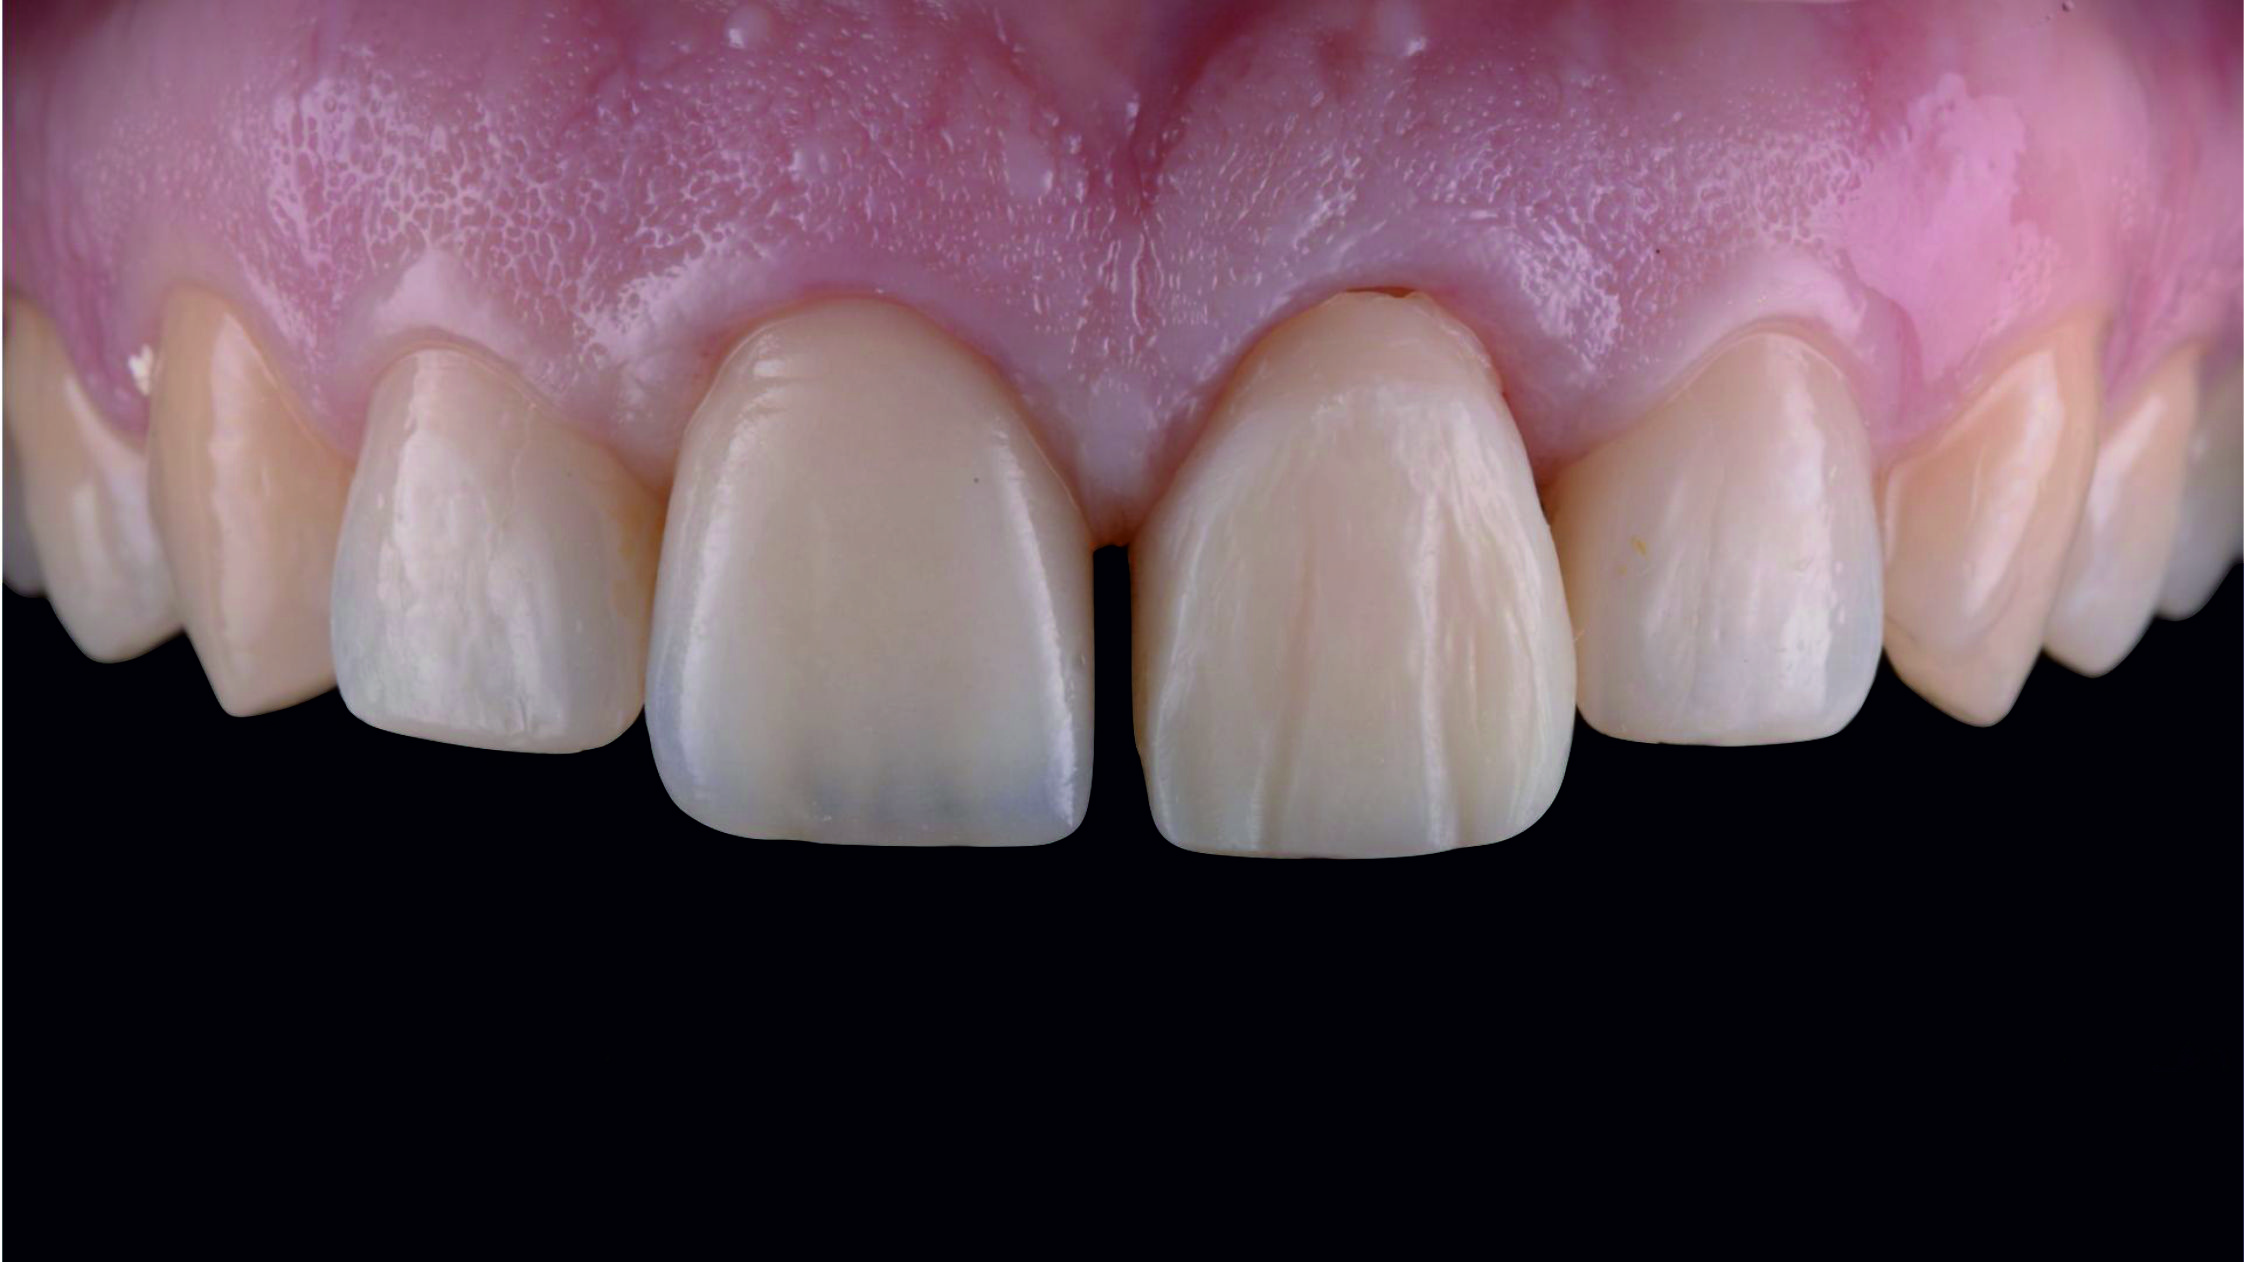

Фото 29. Виготовлені в лабораторії суцільнокерамічні реставрації з дисилікату літію.

Фото 30.

Фото 31. На етапі примірки ми перевірили реставрації щодо відповідності параметрів і форми, розрахованих нами за допомогою тимчасових конструкцій. Для цього ми встановили реставрації поруч одна з одною.

Фото 32. Примірка кінцевих реставрацій.

Фото 36. Вигляд під час повторного візиту за два тижні.

Фото 37. Новий профіль прорізування гарантує здоров'я ясен протягом тривалого часу.Фото 38. Порівняння з початковою ситуацією.